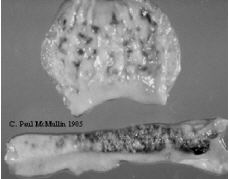

| Figure 28. Severe haemorrhagic and necrotic lesions in proventriculus and Peyers patches in the intestines of a broiler chicken suffering from one of the severe forms of Newcastle disease (viscerotropic velogenic). |

- Necrotic plaques in proventriculus, intestine, caecal tonsil.

- Haemorrhage in proventriculus.

- Intestinal lesions primarily occur in the viscerotropic form.